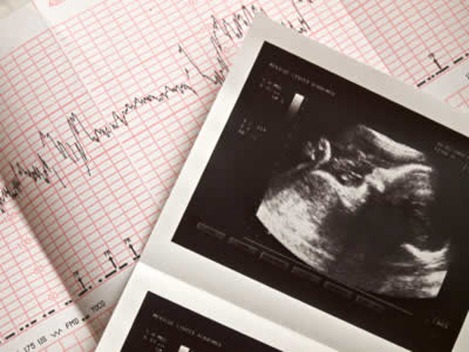

Diagnostico

- El médico realiza estudios maternos de todos los factores que puedan estar involucrados en el retraso del crecimiento. Pruebas como las ecografías eco-doppler, lo ecosonogramas son herramientas útiles.